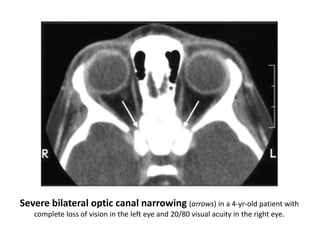

Clinical Features

• Those who survive childbirth present with :

• failure to thrive

• cranial nerve entrapment

• optic nerve compression and blindness,

• facial nerve dysfunction, and

• sensorineural deafness

• snuffling (nasal sinus architecture abnormalities)

• hypercalcaemia

• pancytopenia (anemia, leukopenia and thrombocytopenia)

• hepatosplenomegaly (extramedullary haemopoesis)

• infections of the bones or mandibles

• intracerebral hemorrhage (thrombocytopenia)

• Lymphadenopathy

• A prominent forehead and broad upper skull with

hypertelorism

• One of the commonest presentations is ocular disturbance:

failure to establish fixation, nystagmus or strabismus.

(Searching nystagmus )

Severe bilateral optic canal narrowing (arrows) in a 4-yr-old patient with

complete loss of vision in the left eye and 20/80 visual acuity in the right eye.